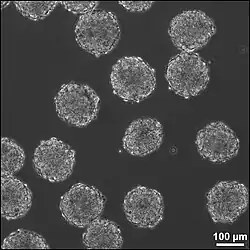

Implantation of stem cells or neural tissue

_images_from_a_Parkinson's_patient_before_and_after_fetal_tissue_transplantation..jpg)

It is possible to artificially create tissue outside of the body to implant into the injury site. This method could treat injuries with large cavities, where a lot of neural tissue needs to be replaced and regenerated. Neural tissue could be grown in vitro with neural stem or progenitor cells in a 3D scaffold, forming embryoid bodies (EBs). These EBs is composed of a sphere of stem cells, where the inner cells are undifferentiated neural cells, and the surrounding cells are more differentiated. 3D scaffolds is for transplant of tissue to the injury site and building the suitable interface between the artificial and the brain tissue. The scaffolds should be biodegradable and biocompatible. It need to fit injury site, close to existing tissue and support growing cells and tissues. The combination of using the stem cells and scaffolds increase the survival of the stem cells in the injury site, increasing the efficacy of the treatment.[64]